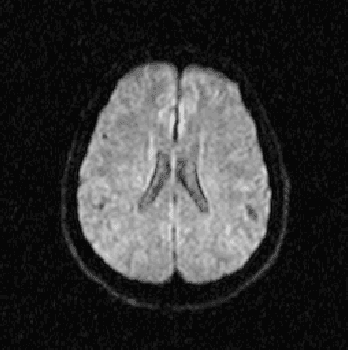

Abstract:Alzheimer's disease is the most common cause of dementia, yet difficult to accurately diagnose without the use of invasive techniques, particularly at the beginning of the disease. This work addresses the classification and analysis of multispectral synthetic images composed by diffusion-weighted magnetic resonance brain volumes for evaluation of the area of cerebrospinal fluid and its correlation with the progression of Alzheimer's disease. A 1.5 T MR imaging system was used to acquire all the images presented. The classification methods are based on multilayer perceptrons and classifiers of radial basis function networks. It is assumed that the classes of interest can be separated by hyperquadrics. A polynomial network of degree 2 is used to classify the original volumes, generating a ground-truth volume. The classification results are used to improve the usual analysis by the map of apparent diffusion coefficients.

Abstract:Alzheimer's disease is the most common cause of dementia, yet hard to diagnose precisely without invasive techniques, particularly at the onset of the disease. This work approaches image analysis and classification of synthetic multispectral images composed by diffusion-weighted magnetic resonance (MR) cerebral images for the evaluation of cerebrospinal fluid area and measuring the advance of Alzheimer's disease. A clinical 1.5 T MR imaging system was used to acquire all images presented. The classification methods are based on multilayer perceptrons and Kohonen Self-Organized Map classifiers. We assume the classes of interest can be separated by hyperquadrics. Therefore, a 2-degree polynomial network is used to classify the original image, generating the ground truth image. The classification results are used to improve the usual analysis of the apparent diffusion coefficient map.